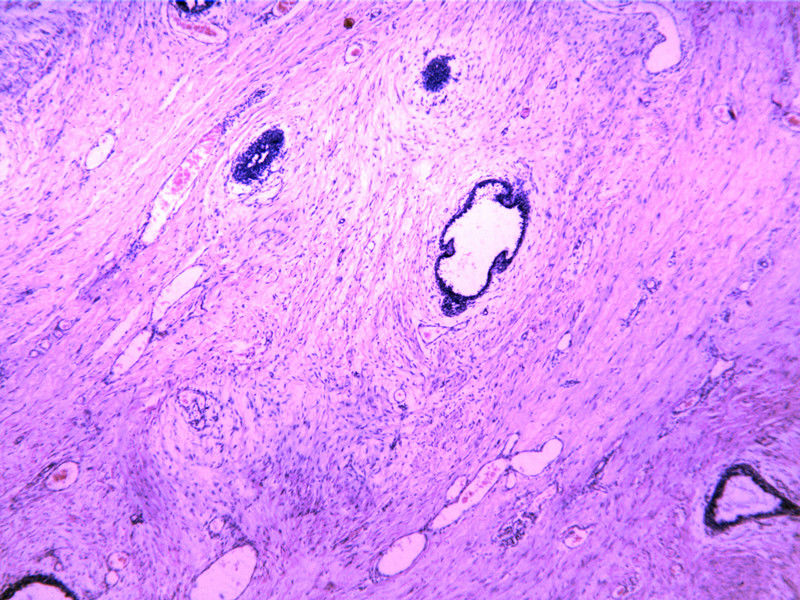

• 包块-无包膜(V4x3x3,79Y)图2

图2

• 包块-无包膜(V4x3x3,79Y)图3

图3

4x3x3(cm?)的包块应该多取几块,“多取材”是解决疑难病例的办法之一。

So far like a benign lesion. FA?